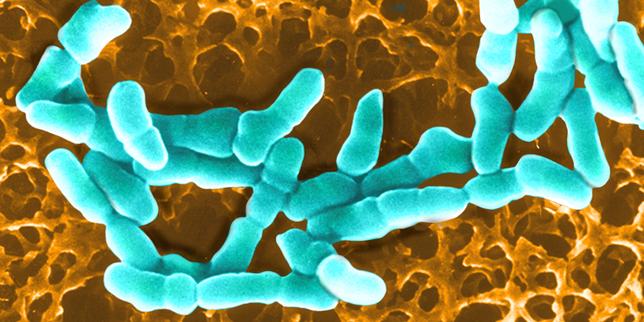

© STEVE GSCHMEISSNER/SCIENCE PHOTO via AFP